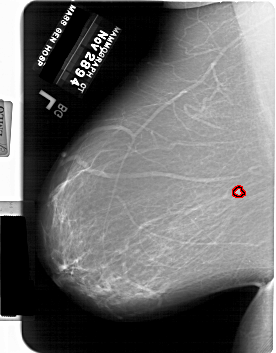

FILE: A_1769_1.LEFT_MLO.OVERLAY

TOTAL_ABNORMALITIES 1

ABNORMALITY 1

LESION_TYPE MASS SHAPE LOBULATED MARGINS ILL_DEFINED

ASSESSMENT 4

SUBTLETY 4

PATHOLOGY BENIGN

TOTAL_OUTLINES 1

BOUNDARY